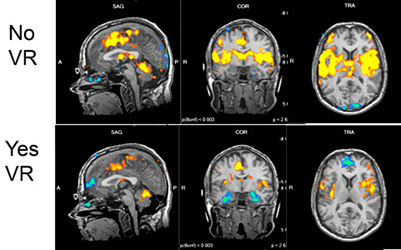

David Rhew is a physician and the Chief Medical Officer at Samsung. During his keynote at MedCity INVEST, he shared the following MRI images to show how patients using VR have less pain than patients who are not using VR. In the images, the yellow areas indicate pain. More yellow means more pain.

Here’s why VR works. Pain requires conscious attention. Conscious attention focuses on pain like a spotlight. But VR immerses patients into a separate world that stimulates the senses, drawing attention away from the pain. Patients feel better without (or with reduced) medication, and without the unpleasant side-effects that drugs produce.